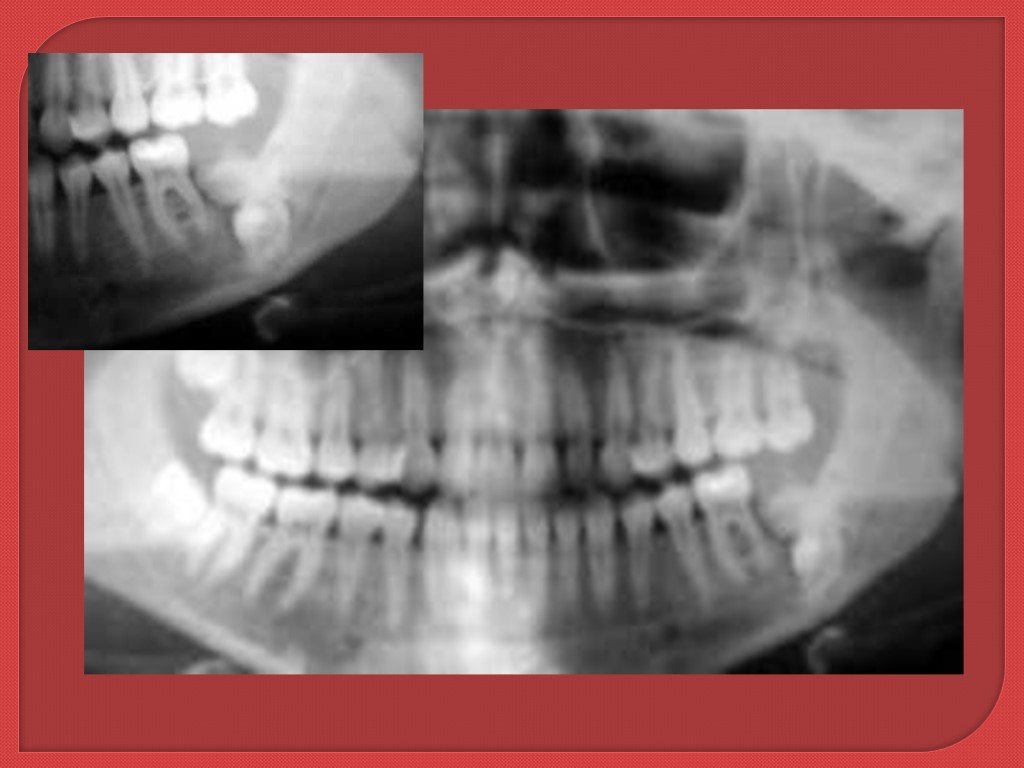

Одонтома нижней челюсти: фотографии и медицинская информация

Раздел: Фотобанк решений